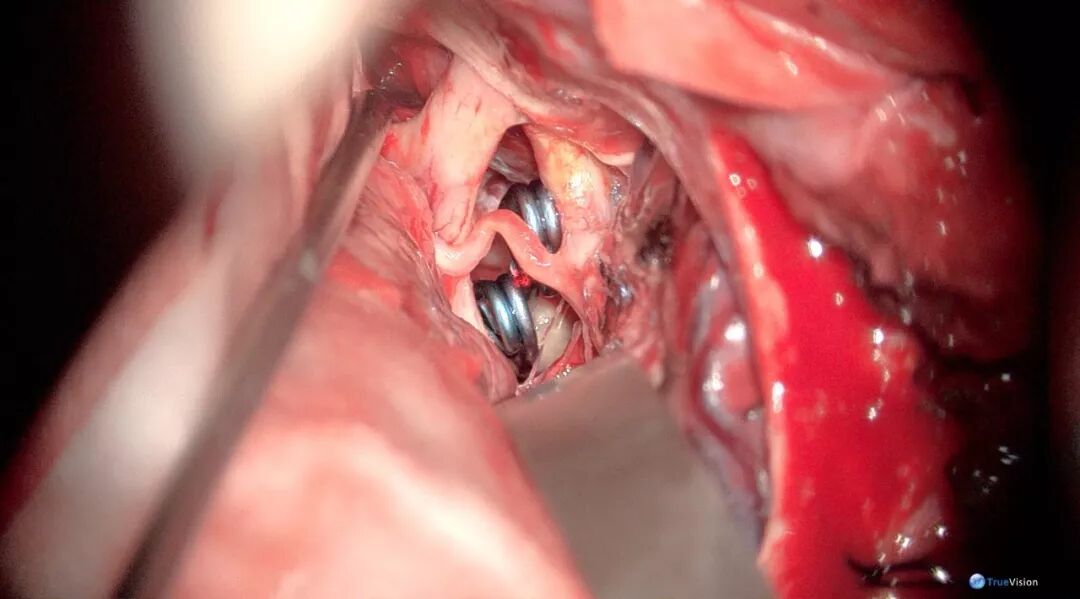

术中图片

图3-3. 第二间隙清除部分蛛网膜下腔出血

图3-4. 暴露出动脉瘤体并进行动脉瘤颈暴露

图3-5. 742动脉瘤夹夹闭瘤颈,探查可见部分动脉瘤体残留

图3-6. 750动脉瘤夹夹闭残留瘤体,确认无载瘤动脉及穿支血管误夹